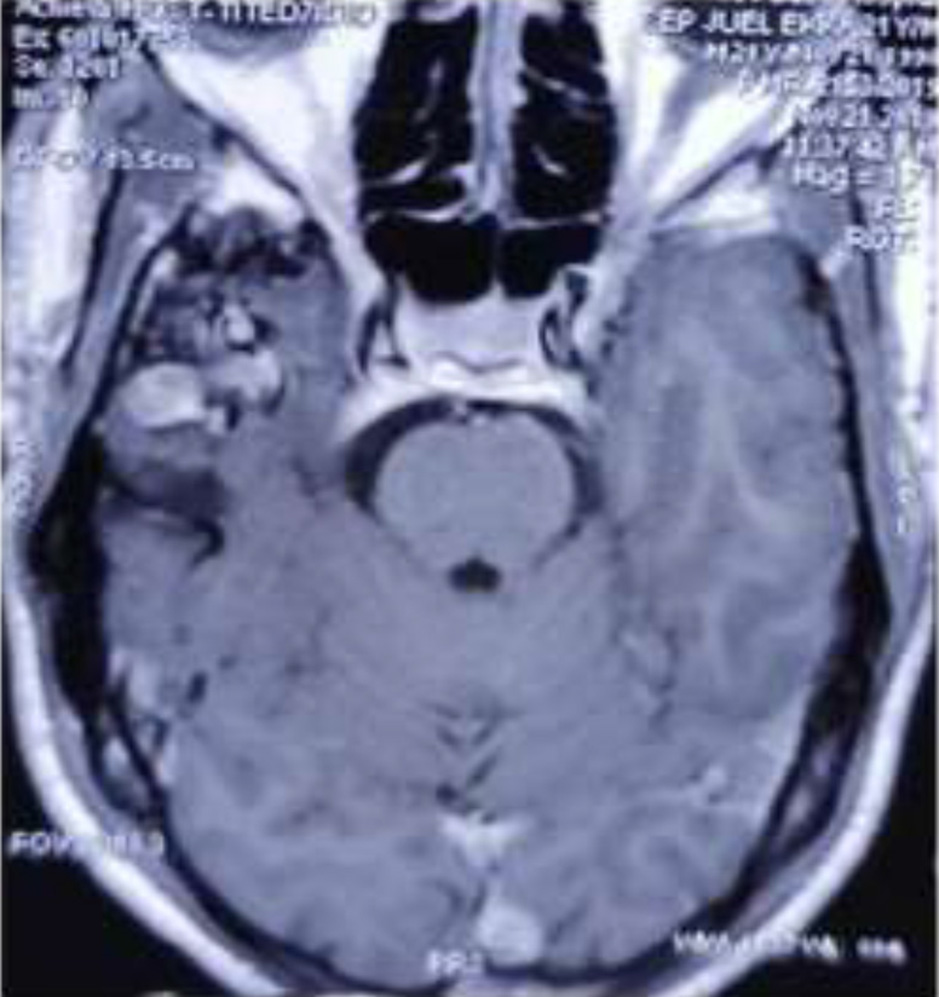

Fig. 2, 3, 4, 5 are the representative images of the patients, showing the AVM, its localisation and planning for purely descriptive purpose only.

Fig. 4. MRI Brain axial view showing AVM in the Right temporal region